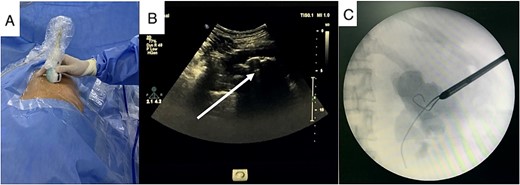

After a thorough assessment, we decided to treat her renal calculi first and deferred treatment of her incisional hernia. A prone mini PCNL was performed using combined ultrasound (US) and fluoroscopy guidance for renal puncture (Fig. 2). After the first session, significant residual stone remained, leading us to perform the salvage PCNL through the original nephrostomy tract and achieve a stone-free result on the C-arm screen. She was discharged on postoperative Day 3 without any complication.

US guidance with carefully exclude bowel during renal puncture (A), real-time US showed the stone and its acoustic shadow (B, arrow), and tract dilation using safety guidewire on fluoroscopy monitor (C).